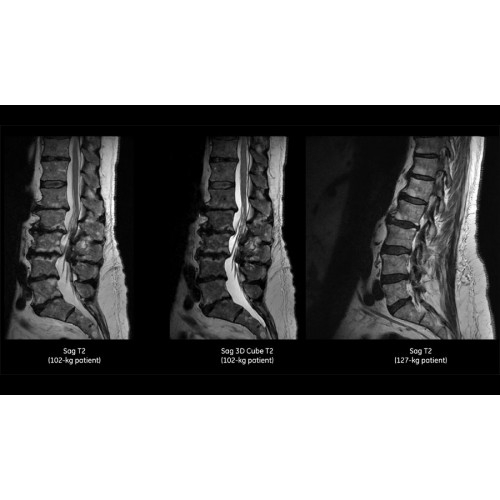

МРТ аппарат GE SIGNA Voyager 1.5T позволяет проводить полный спектр магнитно-резонансных исследований, включая нейровизуализацию, исследования опорно-двигательного аппарата, органов брюшной полости и малого таза, а также специализированные кардиологические программы.